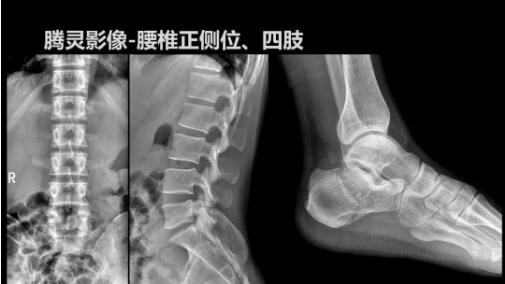

“騰靈”是安健科技的第四代動(dòng)態(tài)DR產(chǎn)品,可實(shí)現(xiàn)全科室應(yīng)用。如各類常規(guī)的X線檢查、消化道檢查、骨科檢查、婦科、兒科檢查等。此外,安健科技為“騰靈”在真正意義上實(shí)現(xiàn)多科室、多功能診斷進(jìn)行了多項(xiàng)針對(duì)性設(shè)計(jì)。

其中包括SID范圍可調(diào)節(jié)能夠滿足多種類攝影要求、球管角度可調(diào)節(jié)能夠滿足不同投照部位的需求、超低床體設(shè)計(jì)方便患者上、下床、360°可旋轉(zhuǎn)腳踏板降低擺位難度、可移除式濾線柵能夠滿足兒科等特定場(chǎng)景的計(jì)量要求、可升降操控臺(tái)方便醫(yī)生床旁操作等,并配置了全身拼接功能,最大程度上適配動(dòng)態(tài)DR產(chǎn)品的特點(diǎn)。

相較前代產(chǎn)品,“騰靈”在圖像質(zhì)量方面得到了全面升級(jí),“騰靈”采用17*17非晶硅平板探測(cè)器設(shè)計(jì),采集矩陣達(dá)3072*3072,動(dòng)態(tài)范圍達(dá)16bit,為成像提供超大視野的同時(shí)保證成像質(zhì)量,此外,該款機(jī)型可根據(jù)醫(yī)療機(jī)構(gòu)的差異化需求而選配不同的動(dòng)態(tài)平板探測(cè)器,以此來(lái)適應(yīng)不同階層用戶所需。